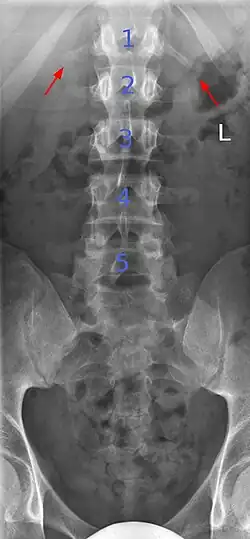

Lumbarization is an anomaly in the spine. It is defined by the nonfusion of the first and second segments of the sacrum. The lumbar spine subsequently appears to have six vertebrae or segments, not five. This sixth lumbar vertebra is known as a transitional vertebra. Conversely the sacrum appears to have only four segments instead of its designated five segments. Lumbosacral transitional vertebrae consist of the process of the last lumbar vertebra fusing with the first sacral segment. [1] While only around 10 percent of adults have a spinal abnormality due to genetics, a sixth lumbar vertebra is one of the more common abnormalities. [2]

Sacralization of the fifth lumbar vertebra (or sacralization) is a congenital anomaly, in which the transverse process of the last lumbar vertebra (L5) fuses to the sacrum on one side or both, or to ilium, or both. These anomalies are observed in about 3.5 percent of people, and it is usually bilateral but can be unilateral or incomplete (ipsilateral or contralateral rudimentary facets) as well. Although sacralization may be a cause of low back pain, it is asymptomatic in many cases (especially bilateral type). Low back pain in these cases most likely occurs due to biomechanics. In sacralization, the L5-S1 intervertebral disc may be thin and narrow. This abnormality is found by X-ray.

Transitional vertebrae have the characteristics of two types of vertebra. The condition usually involves the vertebral arch or transverse processes. It occurs at the cervicothoracic, thoracolumbar, or lumbosacral junction. For instance, the transverse process of the last cervical vertebra may resemble a rib. A transitional vertebra at the lumbosacral junction can cause arthritis, disk changes, or thecal sac compression. Back pain associated with lumbosacral transitional vertebrae (LSTV) is known as Bertolotti's syndrome. One study found that male German Shepherd Dogs with a lumbosacral transitional vertebra are at greater risk for cauda equina syndrome, which can cause rear limb weakness and incontinence.[11]